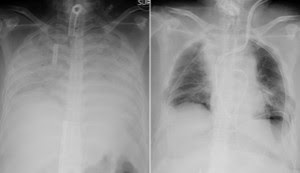

Covid-19 caused so much damage to her lungs they were no longer functional, meaning she required a lung transplant to live.